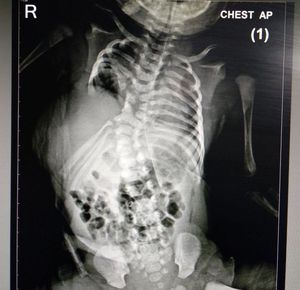

It is Congenital absence of ribs and herniation of liver in to left chest ( diaphragmatic hernia), with flail chest type respiration, cardiac shadow is very well on left side with rib anomalies

Any treatment/prognosis? Is this discoverable with ultrasounds prior to birth?

This condition is also known as Limb body wall complex and can be diagnosed before birth with ultrasound.